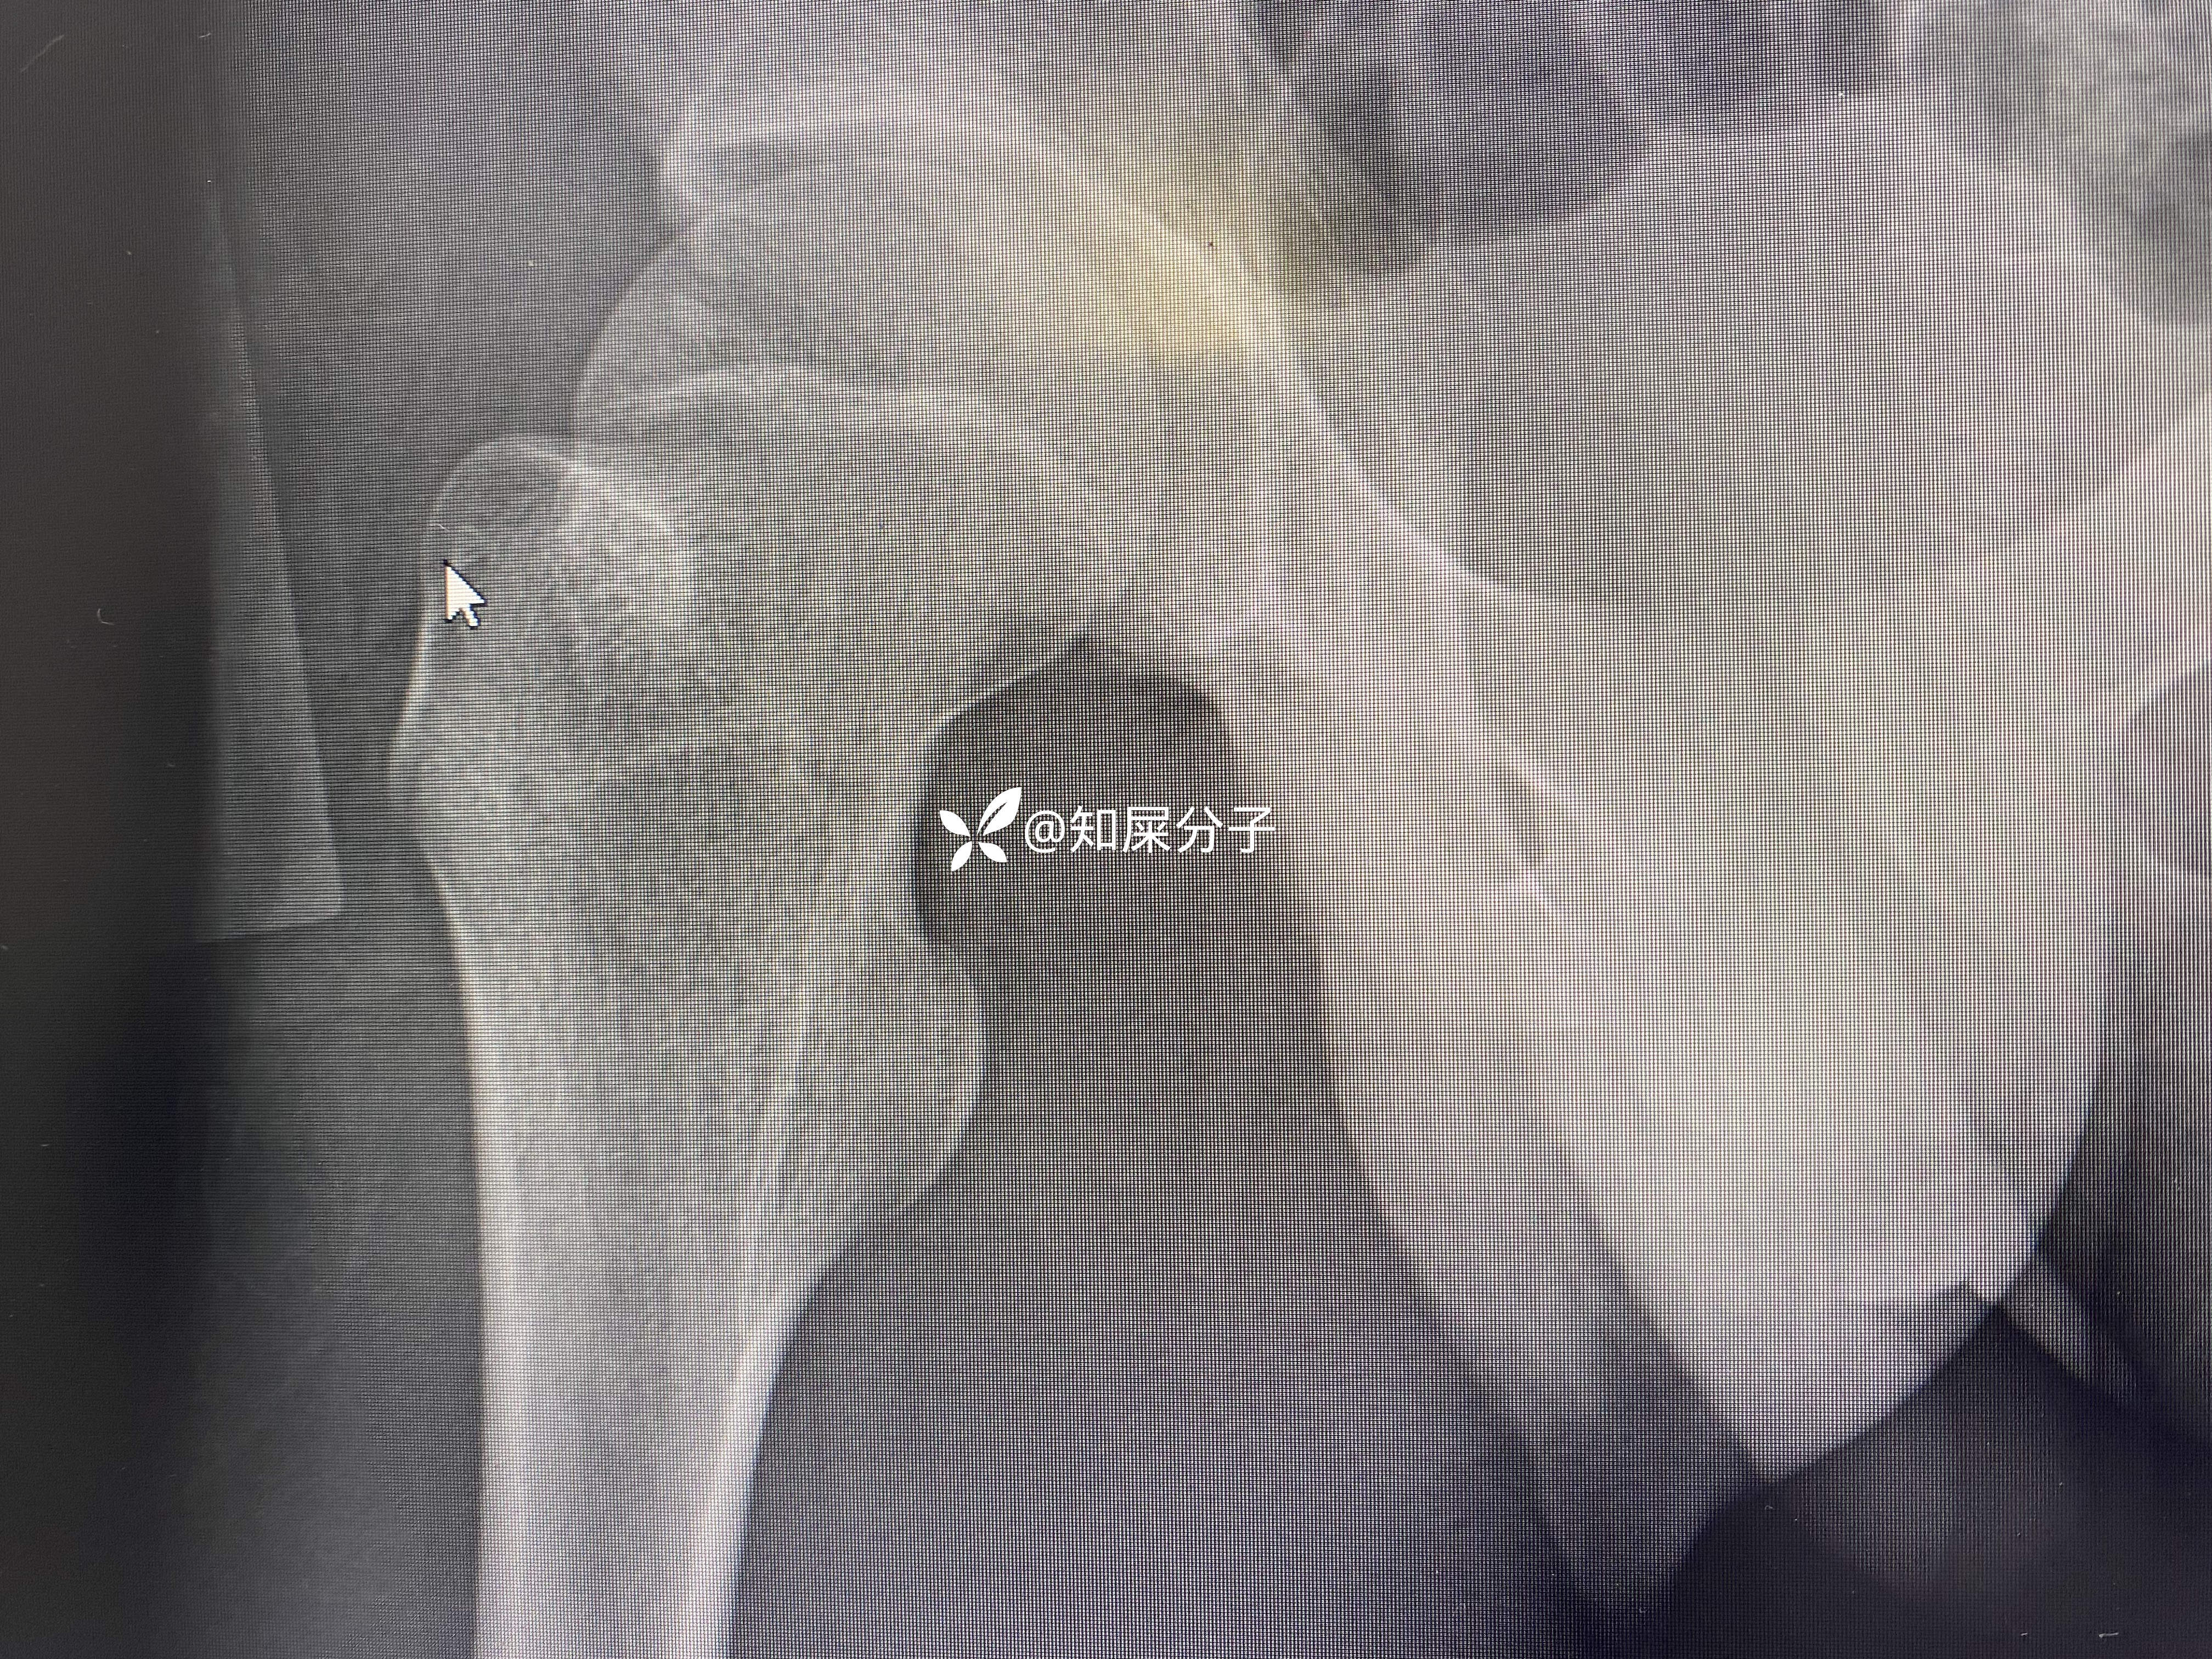

病例股骨颈骨折——青少年

男,17岁

术后如下

你是按儿童的做

按儿童的做几根钉

如何布局螺钉

还是按成人的做?